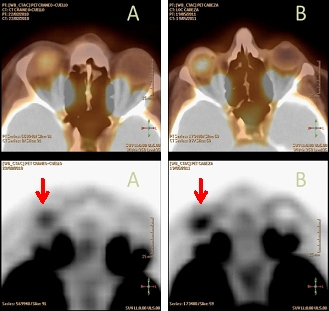

Se trata de un varón de 29 años de edad, diagnosticado de melanoma coroideo en ojo derecho tras pérdida súbita de visión en enero/2010. En febrero/2010 se solicitó una 18F-FDG PET-TC de extensión, donde se visualizó captación patológica focal en lesión intraocular derecha sugestiva de malignidad (fig. 1A); en el resto del estudio no se observaron otros hallazgos de interés.

Posteriormente, en mayo/2011 se solicita nuevo 18F-FDG PET-TC de control evolutivo, donde se observó como único hallazgo de interés, un acúmulo hipermetabólico focal localizado en el interior de la prótesis ocular derecha, en probable relación con actividad inflamatoria debida al tejido de granulación que infiltra la prótesis, no sugestiva de malignidad (fig. 1B). En octubre/2011 se vuelve a solicitar nuevo 18F-FDG PET-TC de control donde se comprueba la persistencia del acúmulo focal descrito previamente en la prótesis ocular derecha (fig. 2), aunque de menor intensidad relativa.